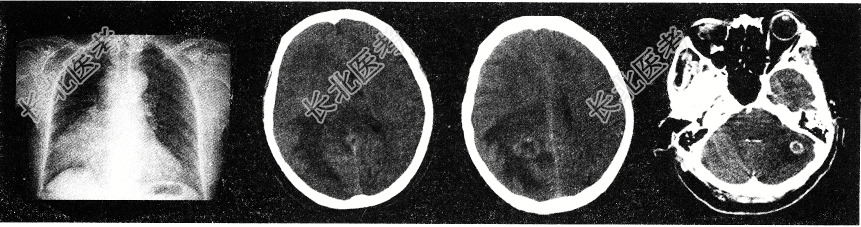

- 单项选择题男性,62岁。既往有右肺腺癌史, 现出现头痛、头晕、恶心、视物模糊,CT检查如图, 最可能的诊断为

C、脑转移瘤